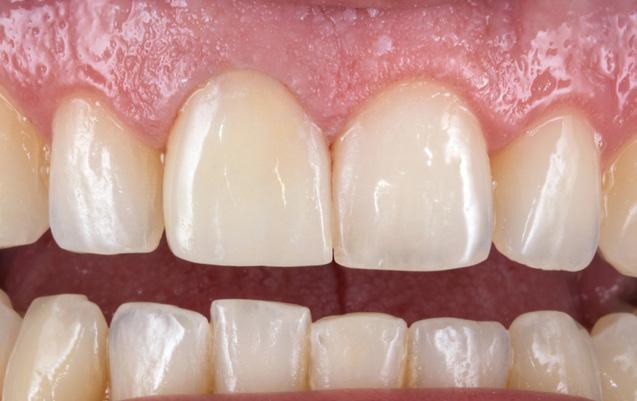

Restoring anterior teeth with large defects using composite seems to be quite challenging. With high-performance materials at hand and a systematic layering concept in mind, however, it is possible to produce highly aesthetic results in a reproducible way. The clinical case below is used to illustrate a dual-shade layering technique with CLEARFIL MAJESTY™ ES-2 Premium, a composite system with pre-defined colour combinations.

The patient, a young male, was unhappy with the appearance of his maxillary anterior teeth. Several years ago, his central incisors had been restored with composite. These existing restorations had defective and heavily discoloured margins, while their shade did not match the adjacent natural tooth structure. The maxillary lateral incisors were peg-shaped (microdontia). Economic considerations and the desire to save as much natural tooth structure as possible made the team decide to restore all four maxillary incisors with composite. CLEARFIL MAJESTY™ ES-2 Premium became the material of choice as it eliminates the need for complicated shade combination formulas and supports predictable outcomes.

An adhesive (CLEARFIL™ Universal Bond Quick) was applied after selective etching of the enamel to achieve a strong bond. With the aid of the silicon index, it was easy to create the palatal shells of the restorations with CLEARFIL MAJESTY™ ES-2 Premium in the shade A3E (enamel), which matches the determined tooth shade A3. The dentin core was built up with the same composite in the recommended shade A3D (dentin), mamelons were modelled and some CLEARFIL MAJESTY™ ES-2 Premium in the shade WD added for the incisal halo, while some individual effects (like enamel cracks) were imitated with brown stain. The build-up was finalized in the interproximal and labial areas with composite in the shade A3E. Between the central incisors, a wedge was used to retract the papilla and facilitate the designing of the interproximal contact area. The finished and pre-polished restorations already had a natural appearance.

Restoring The Lateral Incisors

Tooth preparation was not required on the lateral incisors. Instead, they were merely cleaned after a slight roughening of the enamel surfaces. The build-up procedure was similar to the one used for the central incisors. The adjacent tooth was protected with PTFE tape, and the palatal shell was created with the aid of a finger instead of a silicone index. Afterwards, we focused on the build-up of the interproximal walls before a small amount of dentin was placed and the shape was finalized by applying the labial enamel layer.

Fig. 6 Situation after finalization of the central incisor restorations with composite in the enamel opacity.

Fig. 7 Central incisor restorations after finishing and initial polishing.

Two different opacities, a single shade combination and some bleached shade plus stain for special effects – in the present patient case, a simple formula allowed us to create lifelike anterior restorations. With one enamel and one dentin paste used, it is possible to simply rebuild the natural anatomy without the risk of ending up with a bulky core that – once reduced – will lose its special optical structure. It is also easy to control the thickness of the final enamel layer with its huge impact on the light-optical properties of the whole restoration. For most patients and teeth with a simple or medium-to-complex internal colour structure, the selected concept is very well suited and will lead to pleasing outcomes.

Fig. 10 Final smile of the patient demands.

Fig. 9 Situation after finishing and polishing.